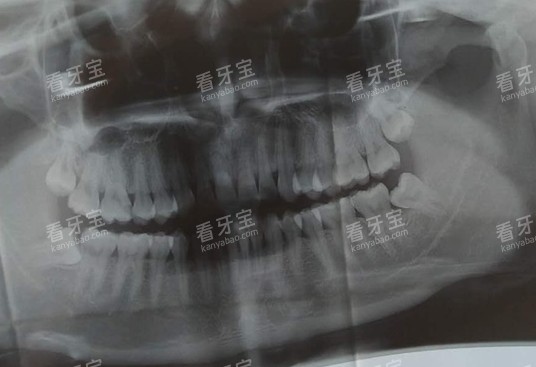

术例二:青少年牙齿正畸术例

患者画像/诉求:李同学,15岁,牙齿排列不整齐,存在龅牙问题,影响了面部美观和自信心,希望通过牙齿正畸改善牙齿排列。

术前问题:李同学的牙齿拥挤程度较高,需要拔除几颗牙齿才能为矫正创造空间。

此外,李同学正处于青春期,学习任务较重,担心正畸治疗会影响学习。

方案:医生为李同学制定了隐形正畸方案,采用了新型的智能化设计技术,为他定制了个性化的隐形牙套。

隐形牙套具有美观、舒适、可自行摘戴等优点,不会影响李同学的日常生活和学习。

改善期反馈:在正畸过程中,李同学按照医生的要求定期更换牙套,并按时复诊。

医生会根据李同学的牙齿移动情况及时调整治疗方案。

李同学逐渐适应了戴牙套的生活,并且看到牙齿逐渐变得整齐,自信心也得到了提升。

结果数据:经过一年多的正畸治疗,李同学的牙齿排列变得整齐,龅牙问题得到了明显改善。

现在,李同学的面部美观度大大提高,他也变得更加开朗自信。